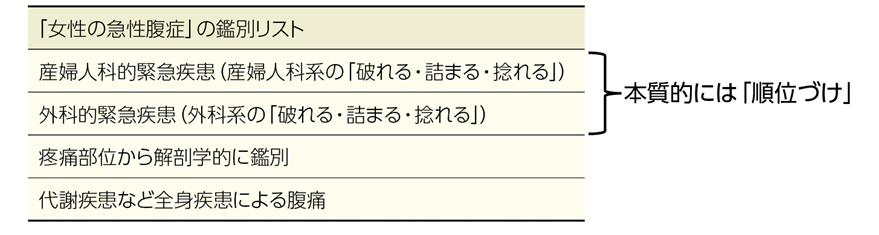

▶ 臨床では患者は様々な情報(症状だったり,検査異常だったり)を帯びて現れる(患者の「プレゼンテーション」)が,生のまま加工していないプレゼンテーションを基に鑑別を考えることは難しい。

▶ たとえば,ある患者のプレゼンテーションが「半年前から食べられる量が減って,痩せたと言われる。1日に5回ほど形のない便が出て,ときどき腹痛もある。ずっとだるさがあって,そういえばあちこちの関節が痛む。近医で血液検査を受けて,貧血と炎症反応の上昇があると言われた」であったとき,この文章からそのまま,論理的に一連の鑑別診断を導けと言われてもちょっと途方に暮れるだろう。

▶ あまりに具体的・個別的な対象は論理的思考の中で扱いにくい。診断というのは患者に表れている具体的な現象を,疾患Aというより一般的な「概念」と一致させることである。これを論理的に行うには,具体的な現象を抽象化・一般化して表現し直す(概念化する)ことがまず必要になる。これが「フレーミング」のキモである(「四つ足で歩き,人間より小さく,全身が毛に覆われ,人懐こくて忠実で愛くるしい生き物」をこの形のまま扱っていくよりも,「犬」という概念に置き換えたほうが「犬」について考えやすい)。

▶ もう少し進めると,フレーミングとは「患者のプレゼンテーションを,抽象的・一般的な医学用語の連なりからなる問題に変形させること」である。こうして定義された問題によって,「可能性のある疾患の範囲を決める枠組み(鑑別のフレーム)」ができる。患者の問題を,そこに拠って鑑別を考えられる形で定義するという意味で,筆者は「問題定義」という言葉も使う。ちょっと砕けた表現をするなら,「〇〇という『くくり』で鑑別を考える」という,「くくり」を決めることだ。

▶ 先ほど,フレーミングとは「患者のプレゼンテーションを,抽象的・一般的な医学用語の連なりからなる問題に変形させること」であると述べた。適切なフレーミングとは,「抽象的・一般的な医学用語の連なりからなる問題」が適切に定義されることである。この際,定義された問題は「診断に関連の強い医学的修飾語句(semantic qualifier)で修飾(qualify)されたhigh yield(後述)なプロブレム」の形をとり,可能なら「症候群化」されているとよい。用語の解説をしつつ,なぜこの形式が「適切」なのかを説明する。